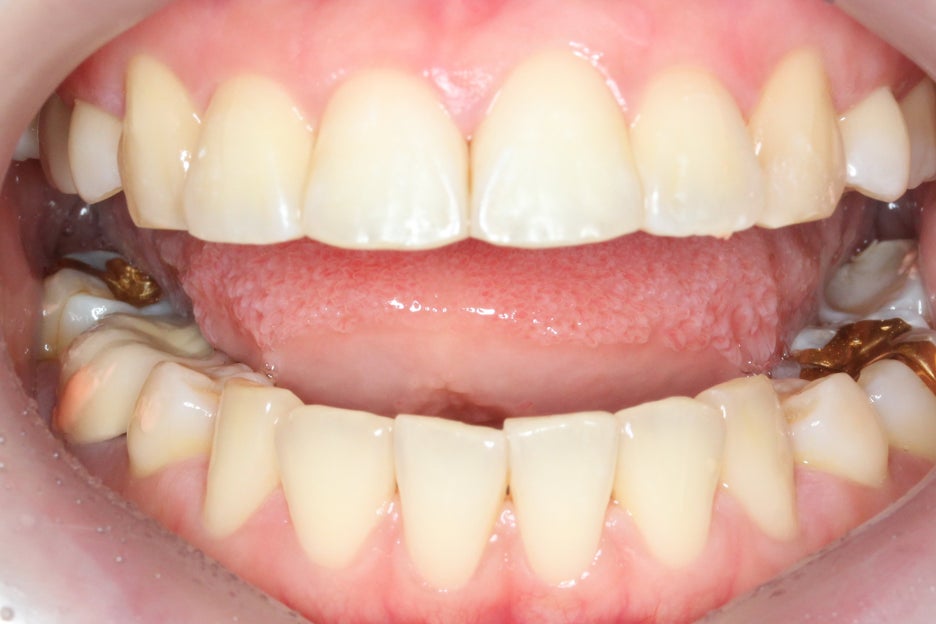

overjet 사진을 보시면

일반적인 Case와 달리

윗니와 아랫니의

돌출차이가 심하고

아랫니가 깊게

물리는 모습을 확인할 수 있습니다.

상하악의 교합면에서도

미세하게 삐뚤거리는

치열을 확인할 수 있는데요,

윗니와 아랫니의 중심이

잘 맞지 않는 상태이기 때문에

부분 교정이지만 최대한

교합을 맞추어 보도록 하겠습니다.